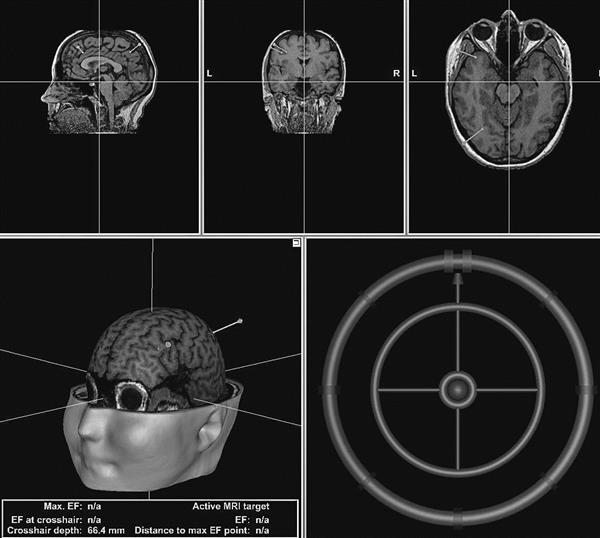

Enim jäi kõlama tõsiasi, et valetamise määraga saab manipuleerida. Veelgi enam, inimest saab magnetimpulssidega mõjutades kas vähem või rohkem valetama panna. Siit edasi tekkis igati mõistetav küsimus: mida sellest laiemas plaanis järeldada? Kas ongi nii, et võime inimese vajaduse korral vaid tõtt rääkima panna? Tõsi, me suutsime valetamise määraga manipuleerida, eksitav on aga tõlgendus, et seda saab teha sedavõrd absoluutsel määral, et üks inimesele omane, mõnel juhul ka ellujäämise seisukohast oluline, käitumine ära kaotada. Aju on selleks piisavalt keeruline ja kompleksne süsteem ning mõningaid valetamisega seotud protsesse seal selliselt tasalülitada, et inimesele mingit kahju ei teki, ei ole ilmselt võimalik. Meie kasutasime oma eksperimentides inimaju stimuleerimiseks ohutut meetodit: elektromagnetiliste impulsside suunamist ajju spetsiaalselt selleks mõeldud aparatuuriga, mis omakorda tähendab, et aparatuur on juba ise oma ohutuse parameetritelt konstrueeritud selliselt, et see mingit ohtu inimesele kujutada ei saa.

Mis oli siiski meie eksperimentide eesmärk? Kas leida võimalus panna inimesi vähem või rohkem valetama? Vastus on jah ja ei. See, mida meie teostasime, oli põhjuslik uuring, et saada teada, kas mõjutades üht kindlat ajupiirkonda on võimalik ka esile kutsuda muutust petukäitumises. See erineb oluliselt senistest sama valdkonna uuringutest, mis on olnud korrelatiivsed, s.t aju aktiivsust on valetamise ajal registreeritud ilma aktiivsust sihipäraselt muutmata. Sellised uuringud ei ütle otseselt midagi selle kohta, kas vastava ajupiirkonna protsessid põhjustavadki valetamist. Tuleb arvestada, et koos valetamisega on aktiivne piirkond kaasatud mitmesse protsessi, nt kontroll, planeerimine jne. Seega oli meie eesmärk saada suuremat selgust, kas see ajupiirkond, mis senistes uuringutes on välja toodud kui valetamisega seotud piirkond, seda ka põhjuslike uuringute põhjal on. Muutus, mille me sel eesmärgil käitumises esile kutsusime, oli valetamise määra vähenemine või suurenemine.

Niisiis on teada, et aju suurte poolkerade üks otsmikusagara eesmisi piirkondi on kaasa haaratud petukäitumisse. Näiteks meie esimeses kahes uuringus, kus eksperimendis osalejatel oli vabalt valida, kas rääkida nähtud objekti kohta tõtt või väita tõele mittevastavat, leidsime, et kui seda piirkonda mõjutada nn väsitavate magnetimpulssidega, siis pärast parema poolkera mõjutamist on keerulisem tõest väidet tagasi hoida ja isikud valetavad vähem. Kui aga pidurdasime vasaku poolkera vastavat piirkonda, siis õnnestus tõese väite tagasihoidmine paremini ning valetamine tuli rohkem esile. Kui aga kasutasime väsitamise režiimi asemel ergastamise režiimi, siis parema poolkera mõjutamise korral õnnestus valetamine katseisikutel paremini. Kui me aga asendasime spontaanse tõe rääkimise teadliku ja motiveeritud valetamisega, siis väsitamise režiim nii selget ja otsest mõju petukäitumisele ei avaldanud. Küll aga tegi seda ergastamine: vasaku poolkera ergastamisel valetamise määr vähenes ja parema poolkera puhul pisut suurenes.

Edasi, kui me võtsime aluseks kahe esimese eksperimendi lähtekohad, panime need kokku ühte katsesse, arendasime seda edasi ja lisasime ajule suuremat pingutust nõudva ülesande, siis leidsid meie eelnenud tulemused vaid osalist kinnitust. Seda ennekõike just stimulatsiooni ergastava mõju osas. Mainitud ülesandes panime objektide vaatlemise ja nimetamise asemel katses osalejad mängima arvutimängu, kus üht liiki objektide – punaste ringide – nimetamise eest oli võimalik koguda punkte, siniste eest otseselt mitte, aga neid „punaseks valetades“ küll; samal ajal kontrollis arvuti vastamist juhuslikel hetkedel ja „vahele jäädes“ võttis punkte maha. Kuna meie kolme uuringu tulemused olid kohati nii omavahel kui varem leituga vastuolus, kerkis uusi küsimusi, mis vajavad uute uuringutega vastuste otsimist. Näiteks, milline roll valetamise kontekstis on ajupoolkeradevahelisel koostööl. Kui üht poolkera väsitada või ergastada, siis kuidas mõjutab see teise poolkera tegevust? Kuidas reageerivad mõjutustele ühes punktis teised petukäitumisse kaasatud nn võrgustiku osad ajus, näiteks need, mis reguleerivad emotsioone, mälu?

Osaliselt neile küsimustele vastust otsides registreerisime oma neljandas eksperimendis, peale ajukoore väsitamise, inimaju aktiivsust valetamise ajal. Ilma mõjutamiseta eksperimendi osas sarnanes registreeritav ajuaktiivsuse pilt seni kirjeldatuga: kui näitasime uurimisalustele arvutiekraanil lavastatud kuriteoga seotud ja mitteseotud objekte – kriitilisi ja neutraalseid stiimuleid –, siis vastuseks kriitilisele stiimulile oli registreeritav ajulaine oluliselt suurema positiivse amplituudiga võrreldes neutraalse stiimuliga. Kui me aga katse eel aju mõjutasime, siis kriitilise stiimuli nägemisega seotud ajupotentsiaali amplituud vähenes ja muutus sarnaseks neutraalse stiimuli tingimustes saaduga. Selline tulemus lisab lootust, et eksperimente jätkates on meil tulevikus võimalik magnetimpulsside toel saada valetuvastuskatsetes täiendavat tuge kriitilise stiimuli paremale äratundmisele ja eristamisele neutraalsetest.